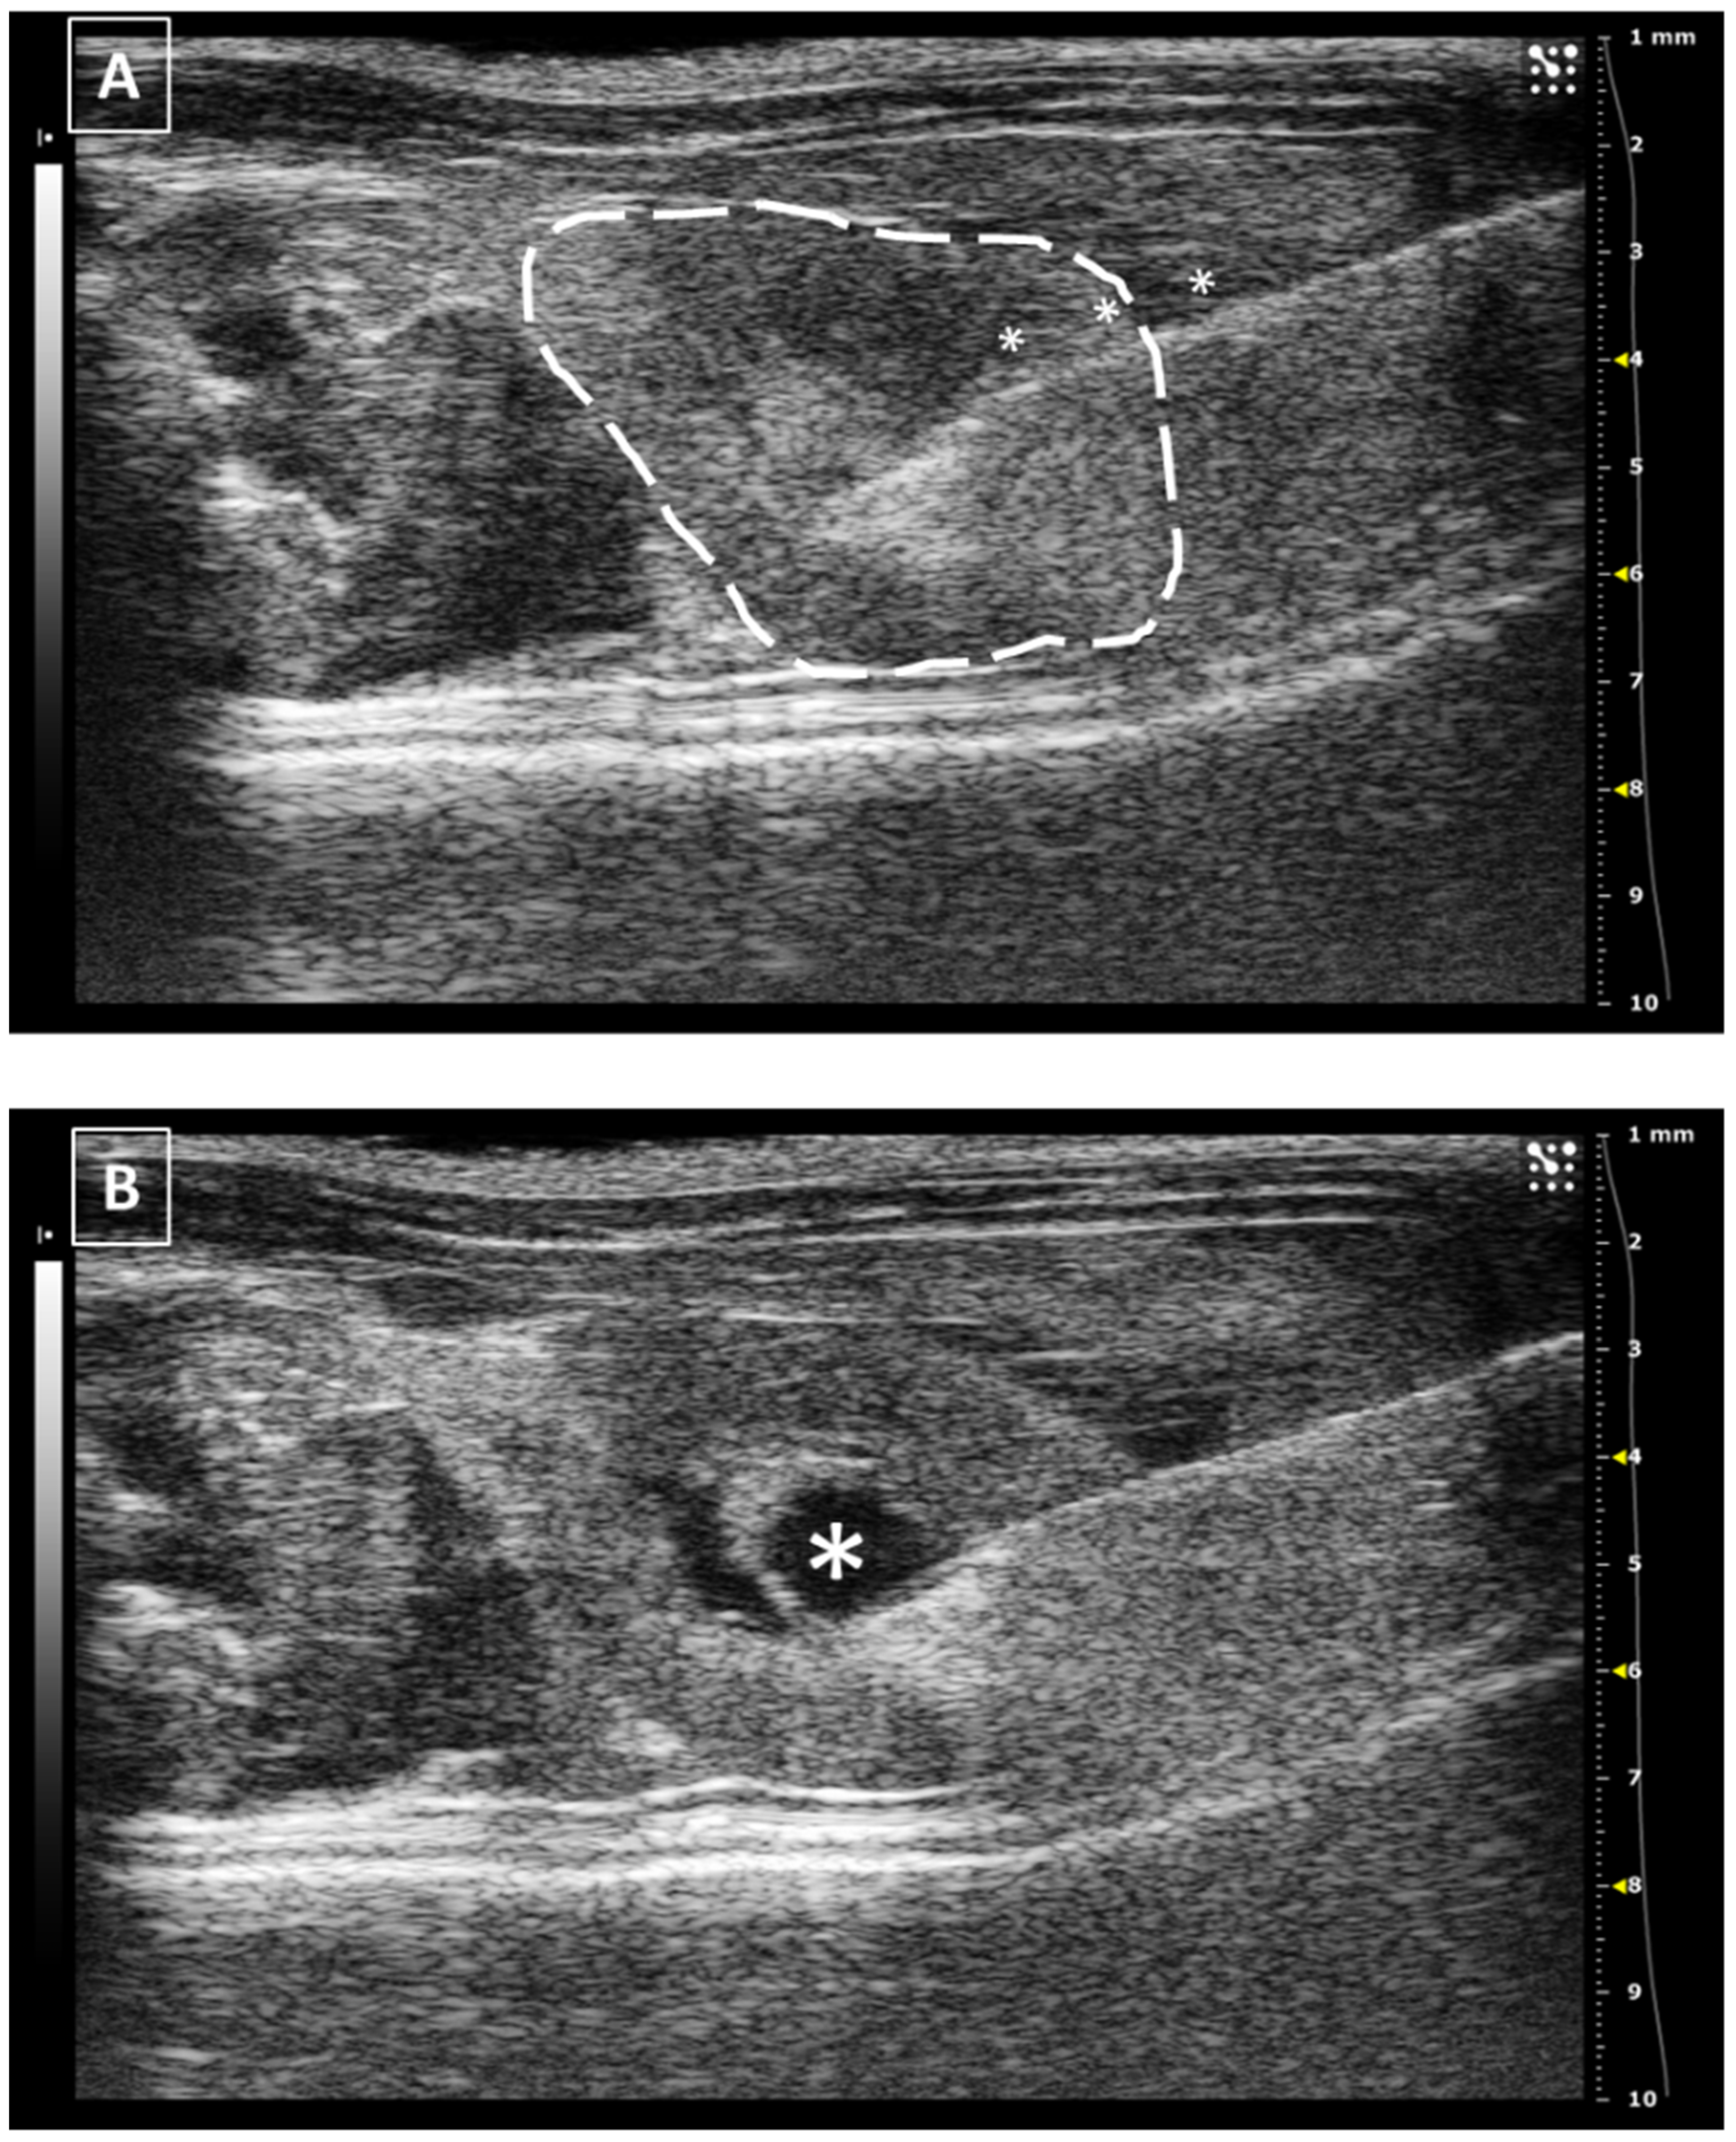

The injected fluid will be observed as a hypoechoic accumulation inside the echoic renal tissue. The maximum volume that we can inject is limited to 20–50 microliters if we attend to the published works [35,36]. The renal tissue is rigid and fragile and does not accept significant increments in the tissular pressure.

In the same way as the liver and spleen, the kidney biopsy can be performed following the same approach as the injection but pulling the needle plunger instead of pushing it down. Multiple samples can be collected in both the cortical and medullar areas of the organ. An example of a renal injection is shown in Figure 7.

The major risk during a renal injection is the incorrect settlement of the fluid. If the injection is performed too deeply into the renal tissue, the tip of the needle could reach the pelvic zone. In this case, the injected fluid will be released directly into the pelvic area and moved to the ureters. Another risk of incorrect injections could be injecting into the renal vessels, especially the renal vein, bigger than the artery. But this possibility is low if we make a safe approach from the lateral or dorsum.

Figure 7. Intrarenal injection. (A) Injection of the needle into the kidney. Needle is marked with white asterisks and the kidney is surrounded by a dashed line. The injection is performed in the medullar zone of the organ. (B) Administration of the fluid, that is marked with a white asterisk. Images obtained at 40 MHz frequency.